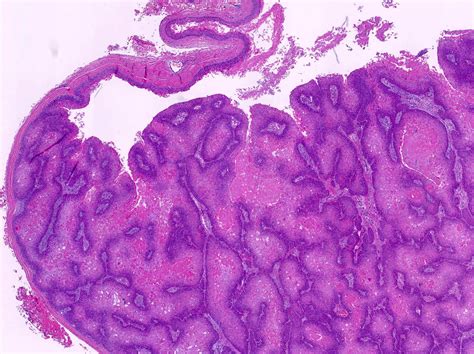

Identifying Trichilemmal Cysts Through Images

Trichilemmal cyst images are invaluable for identifying and diagnosing these cysts. These images can help healthcare providers and individuals recognize the characteristic appearance of trichilemmal cysts. Key features to look for in trichilemmal cyst images include:

• A well-defined, round or oval lump under the skin.

• A smooth, shiny surface that may be skin-colored or slightly yellowish.

• No visible opening or pore on the surface of the cyst.

• In some cases, the cyst may appear red or inflamed if infected.

Below is an example of what trichilemmal cyst images might look like:

Trichilemmal Cyst Images